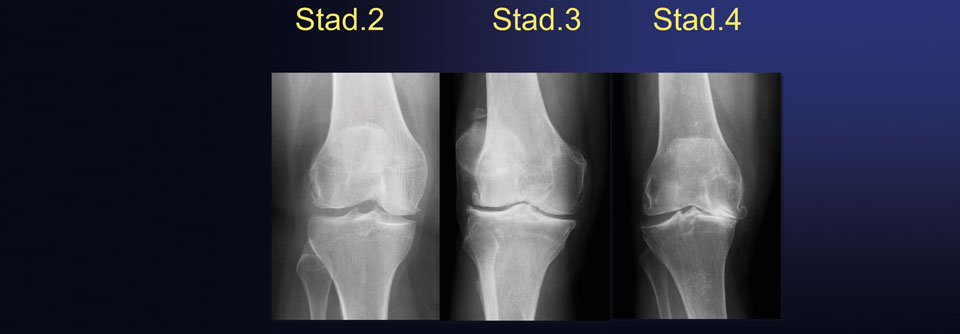

Arthrose-Patient:innen leiden oft unter Schlafstörungen durch Schmerz, Schlafstörungen können aber auch die Arthrose-Entstehung fördern. Arthrose-Patient:innen leiden oft unter Schlafstörungen durch Schmerz, Schlafstörungen können aber auch die Arthrose-Entstehung fördern. © peerayot – stock.adobe.com

Patienten mit Fibromyalgie und Arthrose berichten häufig über gestörten und wenig erholsamen Schlaf. Es gilt, den Teufelskreis aus Schmerzen, Schonverhalten und Müdigkeit zu durchbrechen.

Mehr als zwei Drittel aller Patienten mit Arthrose leiden unter Schlafstörungen. Das Risiko für schlechten Schlaf liegt  bei ihnen mehr als doppelt so hoch wie bei Gesunden. Bei 31 % ist die Latenz bis zum Einschlafen verlängert, 81 % schlafen nicht durch. Jeweils rund die Hälfte klagt über morgendliches Früherwachen oder generell unzureichenden Schlaf. Im Wesentlichen ist es natürlich der Schmerz, der Patienten mit Arthrose und Fibromyalgie die Nachtruhe raubt, erläuterte Prof. Dr. Christoph­ Baerwald­, Klinik und Poliklinik für Gastroenterologie und Rheumatologie an der Universitätsklinik Leipzig. Frauen sind häufiger betroffen als Männer, Menschen mit geringem Einkommen öfter als…